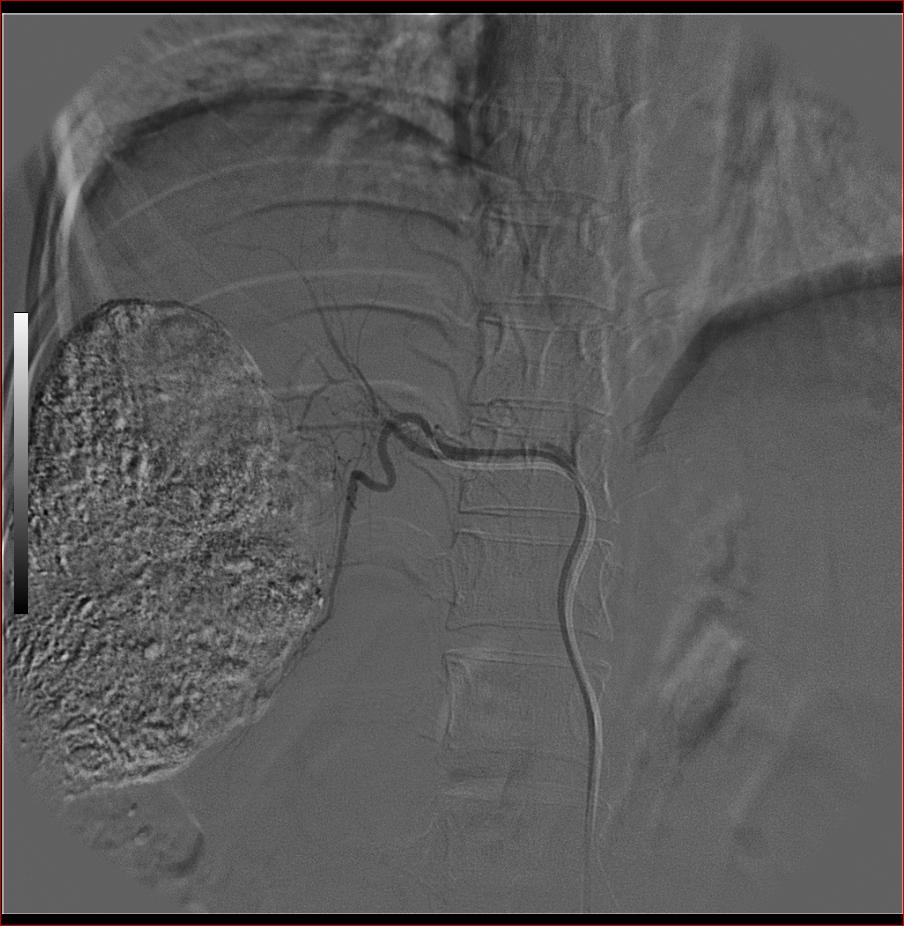

第二次(50天后)

栓塞的非常理想。

巨块型肝癌介入术后,肝左叶有转移吗(第二次进行肝左动脉栓塞了吗?)